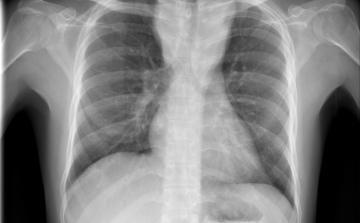

Egy líbiai menekülttáborból érkezhetett Európába a tbc egy új kórokozója

Menekültek révén, egy líbiai táborból érkezhetett Európába a tuberkulózis (tbc) kórokozójának egy korábban ismeretlen, gyógyszerekkel szemben ellenálló fajtája - írta a Die Welt című német lap a hírportálján szerdán.

Csökkent a tbc-fertőzések száma Európában

Átlagosan 4,3 százalékkal csökkent az új tuberkulózisos (tbc-s) esetek száma 2010 és 2014 között az Egészségügyi Világszervezet (WHO) 53 országot magába foglaló európai régiójában.